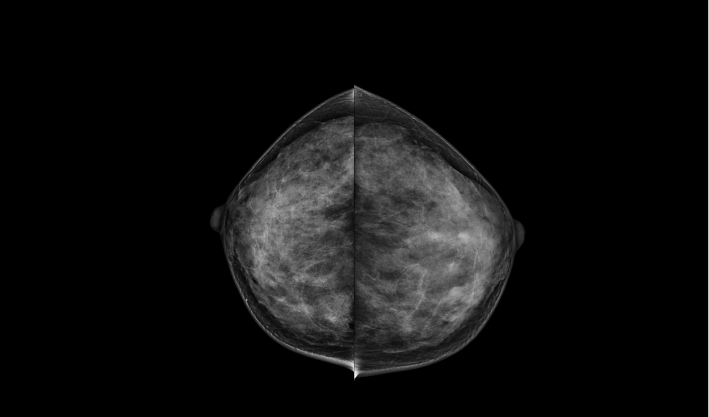

头尾位(CC位) 内外斜位(MLO位) 补充体位(根据需求)

一键式视图切换